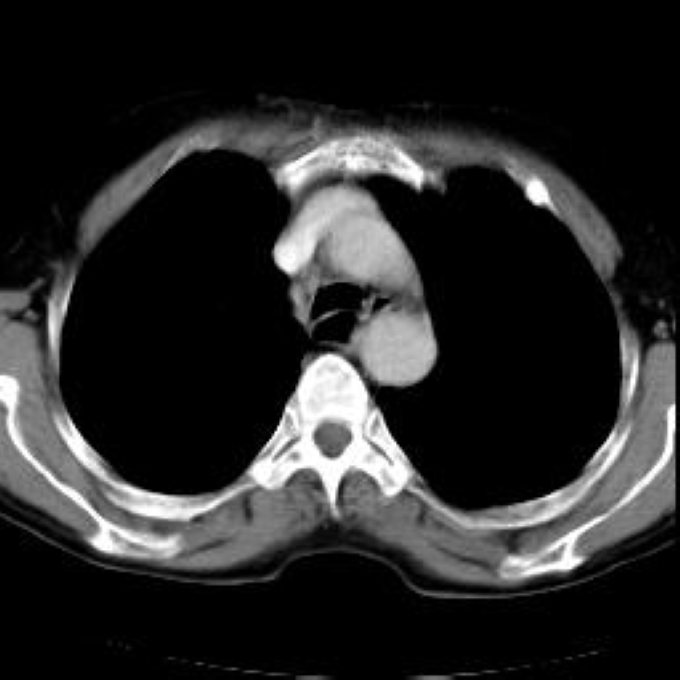

Arteria lusoria.

56 year old patient with dyspagia. A tumor of soft tissue was described in upper mediastinum on plain X-ray of the thorax. What is this mass in the upper mediastinum?